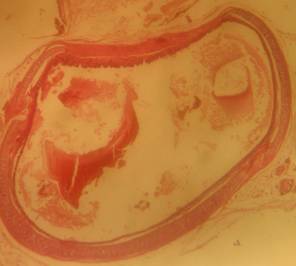

Morphological structure of aorta’s rats

Aorta’ slide was made every week for one month. Each group of the rats was killed, and the aorta’s rat was observed. From the morphological structure of aorta’s rat, atherosclerosis was scored as follows: on 4 point: 0, normal; 1, widening of elastic fibers with few foam cells; 2, fragmentation of elastic lamellae with numerous foam cells and fibrosis; 3, smooth muscle cells proliferation, medial lipid infiltration and fibrosis; 4, lipid-calcic plaque or ulcerated plaque [10].

Table 1: Distribution of aortic atherosclerosis scores at D90 in two groups of rat receiving atherogenic diet (n = 4)

| Lesions scores | A1 | A2 | A3 | A4 | B1 | B2 | B3 | B4 | C1 | C2 | C3 | C4 | D1 | D2 | D3 | D4 |

| 0 | - | - | 1 | 3 | - | - | - | 2 | - | - | - | - | 3 | 4 | 3 | 3 |

| 1 | 1 | 3 | 3 | 1 | 1 | 1 | 2 | 2 | 2 | - | - | - | - | - | 1 | 1 |

| 2 | 3 | 1 | - | - | 2 | 1 | 1 | - | - | 1 | 1 | 1 | - | - | - | - |

| 3 | - | - | - | - | 1 | 2 | 1 | - | 2 | 2 | 1 | 1 | - | - | - | - |

| 4 | - | - | - | - | - | - | - | - | 1 | 2 | 2 | - | - | - | - |

A1, A2, A3, A4 is morphological structure of aorta’s AND rats fed atherogenic diet for 2 mo and continuing with AND for 1 w, 2 w, 3 w and 4 w; B1, B2, B3, B4 is morphological structure of aorta’s atorvastatin rats fed atherogenic diet for 2 mo and continuing with atorvastatin for 1 w, 2 w, 3 w and 4 w; C1, C2, C3, C4 is morphological structure of aorta’s rats fed atherogenic diet for 9th week, 10th week, 11th week, 12th week; D1, D2, D3, D4 is morphological structure of aorta’s rats fed normal diet for 9th week, 10th week, 11th week, 12th week.

The rats (n=4) from each group were sacrificed every week to observe the morphological structure of the aortas. From the lesions, it showed that AND could help chance severity aortic atherosclerosis. The score varied from group A1 until group A4. The aorta morphology of group A1 showed that one aorta had a widening of elastic fibers with few foam cells (score 1) and three aortas had the proliferation of smooth muscle cells (score 3) (fig. 5 A1). AND administration for four weeks could repair aorta condition. Group A4’ aorta morphology showed that three aortas became normal (score 0) and one aorta still had a widening of the first interlamellar (score 1) (fig. 5 A4). Atorvastatin administration could also help changing the severity of aortic atherosclerosis. The score also varied from group B1 until group B4. The aorta morphology of group B1 showed that one aorta had a widening of elastic fibers with few foam cells (score 1), two aortas had fragmentation of elastic lamellae with numerous foam cells and fibrosis (score 2), and one aorta had the proliferation of smooth muscle cells (score 3) (fig. 5 B1). Atorvastatin administration for four weeks could improve aorta condition. Group B4’ aorta morphology showed that two aortas became normal (score 0) and two aortas still had a widening of the first interlamellar (score 1) (fig. 5 B4). Contrarily, the morphological structure of atherogenic rats was getting worse week by week.

Fig. 5: Morphological structure of aorta in albino Wistar male rats 40x. A1, A2, A3, A4 is morphological structure of aorta’s AND rats fed atherogenic diet for 2 mo and continuing with AND for 1 w, 2 w, 3 w and 4 w; B1, B2, B3, B4 is morphological structure of aorta’s atorvastatin rats fed atherogenic diet for 2 mo and continuing with atorvastatin for 1 w, 2 w, 3 w and 4 w; C1, C2, C3, C4 is morphological structure of aorta’s rats fed atherogenic diet for 9th week, 10th week, 11th week, 12th week; D1, D2, D3, D4 is morphological structure of aorta’s rats fed regular diet for 9th week, 10th week, 11th week, 12th week. Black circle (O) = score 1; green circle (O) = score 2; red circle (O) = score 3; blue circle (O) = score 4